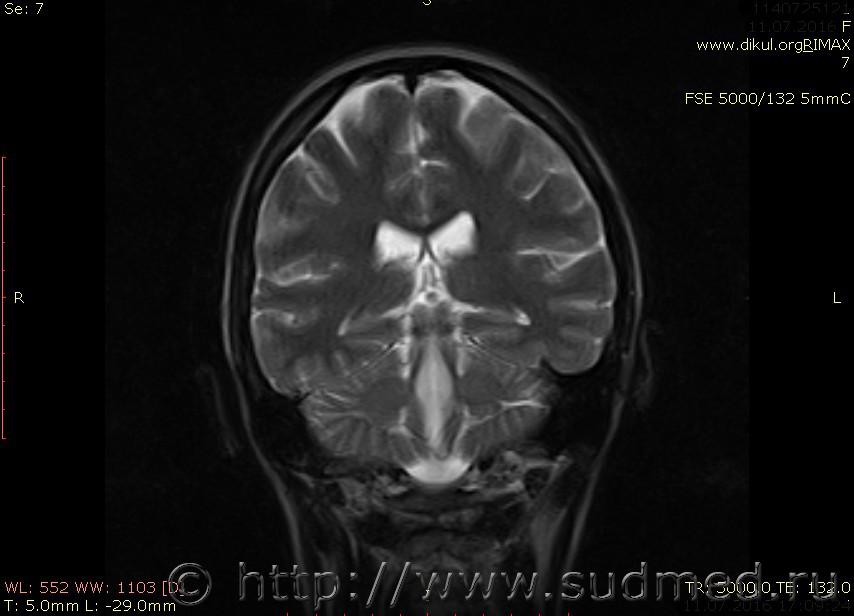

МРТ головного мозга показало: МР-данных за наличие очаговых изменений в веществе головного мозга на момент исследования не выявлено. МР-признаки нарушения соотношения в атланто-осевом суставе. Определяется ассиметрия положения зубовидного отростка С2 относительно боковых масс С1(справа 6,5; слева 4 мм.)

Сама по себе эта информация даёт основания подозревать вывих первого шейного позвонка, но однозначно не свидетельствует о наличии вывиха. Нужно смотреть на снимках наличие реакции со стороны мягких тканей, в т.ч. связочного аппарата, нужно анализировать особенности неврологической патологии, её динамику и проч.

Запрошен электронный вариант снимков из учреждения, где делалось МРТ. Т.к. с самого снимка делать копии не получается,очень мелкие кадры. Завтра попробую вставить в сообщение. (Но СМЭ снимок не смотрел, смотрел только мед.карту, в которой находилось описание МРТ).

Посмотрите пожалуйста снимки, надеюсь на них видны позвонки С1,С2?

Прошу прощения, попробую снова прикрепить файлы. Данные учреждения и пациента убраны.